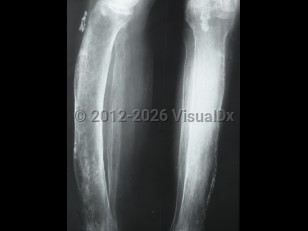

Inflammation of the periosteum, the covering of bones. Generally chronic, but may be acute.

- Chronic – Manifests with tenderness and swelling of the bone and an aching pain, and may be due to systemic inflammatory disorders.

- Noninfectious acute – Shin splints in athletes is a common cause.

- Infectious acute – Typically manifests with diffuse suppuration, severe pain, and systemic symptoms; it often results in necrosis.